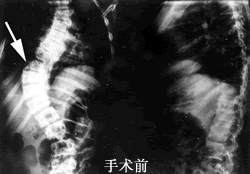

一位11岁少女,因患先天性脊柱严重侧弯达60度,而呈“蛇形”。近日,河北医科大学第三医院骨科王汉林教授等为其行全麻下脊柱侧弯经胸前路凸侧软组织松解、骨骺融合、双侧骨髁牵引术;待患儿体质稳定后,又在全麻下为其行脊柱后路矫形、双杠多钩内固定植骨融合加胸廓成形术。术后患儿脊柱侧弯角度明显缩小,外观接近正常,生活质量等得到根本性提高。